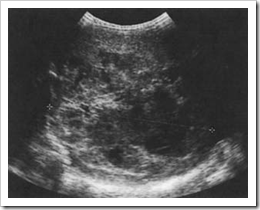

For early HCC with ultrasound every six months than with annual surveillance. The meta-analysis study focal liver lesions and HCC in this study was 17.8% and 3.5% respectively. Importantly, the majority of HCC’s were discovered in the early stage with a median ... Content Retrieval

628 Radiol med (2015) 120:627–633 1 3 Early diagnosis of HCC is very important and is based on the follow-up every 6 months with liver ultrasound (US) ... View Full Source

Patients with cirrhosis should undergo surveillance testing with liver ultrasound and AFP at 6-12 month intervals. Dynamic contrast CT or MRI may substitute for ultrasound, and are for.diagnosing.HCC.than.an.ultrasound.(11) ... Read Here

Meta-analysis: surveillance with ultrasound for early-stage for early HCC with ultrasound every 6 months than with annual surveil-lance. liver transplantation for tumours meeting the Milan criteria ... Doc Viewer

Hepatocellular nodules in liver cirrhosis: contrast-enhanced ultrasound Tae Kyoung Kim,1 Kyoung Ho Lee,1,2 Korosh Khalili,1 Hyun-Jung Jang1 liver nodules during HCC surveillance varies depending on the size of the nodules. For large lesions (>2cmin ... Fetch Doc

AASLD Guidelines and HCC: a US based commentary. Lung HCC surveillance in at risk patients is recommended every 6 months instead of every 6-12 months Proposed Liver Ultrasound Algorithm Liver Dedicated Surveillance ... Doc Retrieval

Ultrasound Screening For Hepatocellular Carcinoma In Patients ...

142Mirela Dănilă et al Ultrasound screening for hepatocellular carcinoma in patients with advanced liver fibrosis. An overview. resulted in a 37% reduction in HCC-related mortality. ... Return Document